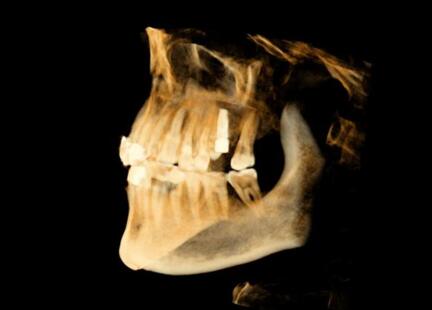

術(shù)后精度驗(yàn)證

種植體類 型植入點(diǎn) 末 端角 度

26 計(jì)劃<->實(shí)際 0.88 0.96 2.68